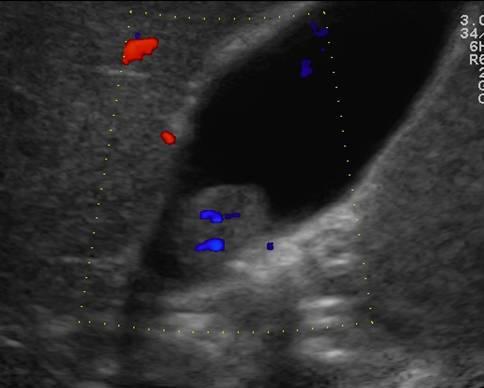

Ung thư túi mật

Ung thư túi mật - Ảnh 4

» Thông tin: Nam giới – 75 tuổi.

» Lâm sàng: Đau mạn sườn phải.